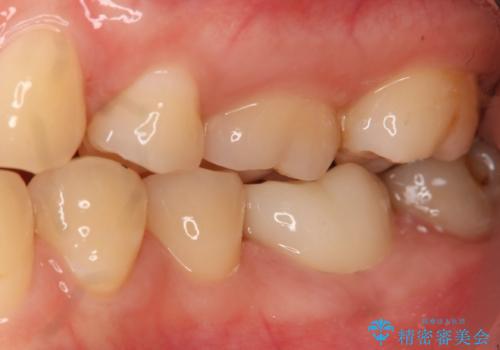

左下奥歯が腫れて痛い フルジルコニアクラウン

- 左下大臼歯の歯肉に腫れと痛みが繰り返し起こっているので治療を希望し来院された患者様です。

既に治療されている歯でしたが根尖部に病巣が確認出来たので、精密根管治療とクラウンの再治療が必要と判断されました。

精密根管治療を行なったことで病巣は消失し、腫れや痛みは再発することなく経過は良好です。

被せ物はフルジルコニアクラウンを選択されました。